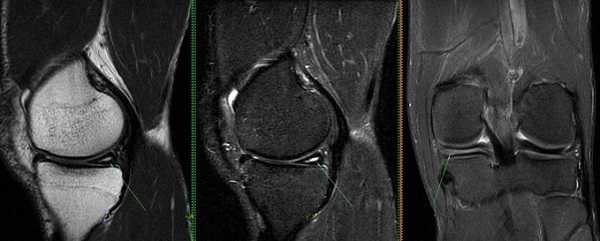

Схематическое изображение изменений мениска на МРТ согласно классификации Stoller.

0 степень (норма), мениск без изменений.

I степень — шаровидное повышение интенсивности сигнала, не связанное с поверхностью мениска.

II степень — линейное повышение интенсивности сигнала, не связанное с поверхностью мениска.

III степень (разрыв) — повышение интенсивности сигнала, соприкасающееся с поверхностью мениска. Возможно выделение III a степени, когда разрыв распространяется до одного края суставной поверхности мениска, и III bстепени, когда разрыв распространяется до обоих краев мениска.

В зависимости от степени повреждения на снимках МРТ в режиме Т2 видны:

- очаг повышения интенсивности сигнала шаровидной формы, не связанный с поверхностью мениска (I стадия);

- светлый участок линейной формы, не затрагивающий хрящевой край (II стадия);

- повышение интенсивности сигнала распространяется на одну (III a) или обе (III b стадия) суставные поверхности пластины.